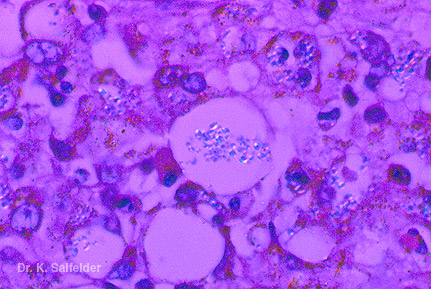

Abb. 9,27: Histoplasmose

Dieselbe Zelle im polarisierten Licht. HE-Faerbung